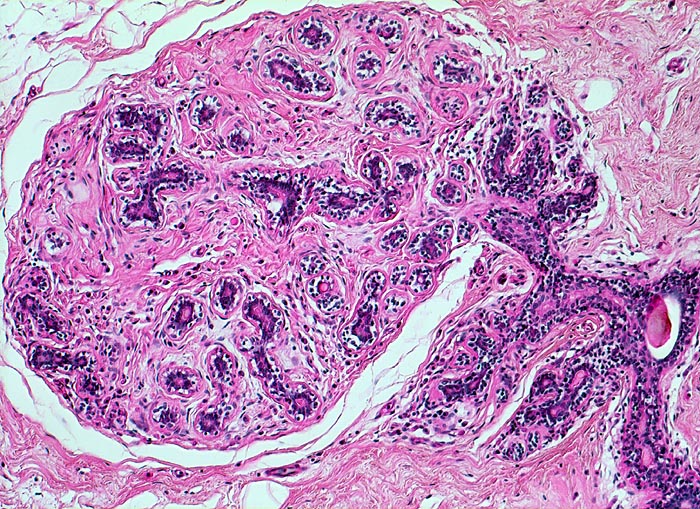

In der Mitte rechts einige Gänge mit gewöhnlicher intraduktaler Epithelhyperplasie ohne Atypie: Polymorphe, sich überlagernde spindelige Zellen. Fliessende Anordnung der Zellen. Schlitzförmige und irregulär geformte Lumina.

Herdförmig apokrine Metaplasie des Drüsenepithels: hochprismatische Zellen mit sehr reichlichem feingranulärem eosinophilem Zytoplasma und runden Kernen.

Alle Drüsen zeigen eine erhaltene äussere abgeflachte Myoepithelschicht mit hellem Zytoplasma.